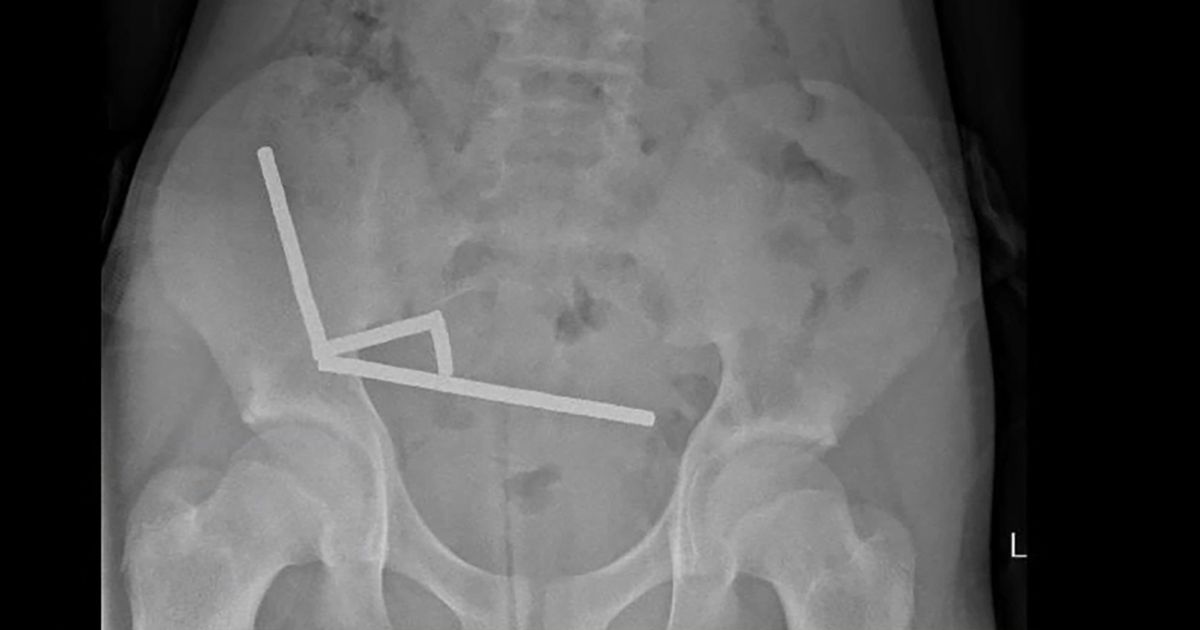

وقال مسعفون إن المغناطيسات فائقة القوة، المحظورة في نيوزيلندا منذ يناير/كانون الثاني 2013، تم شراؤها من السوق الصيني عبر الإنترنت “تيمو”. كانت المغناطيسات الصغيرة على شكل كريات ملتصقة معًا في أربعة شرائح طويلة داخل أمعاء الطفل.

وقال التقرير: “يبدو أن هذه (الشرائط) كانت في أجزاء منفصلة من الأمعاء ملتصقة ببعضها البعض بسبب القوى المغناطيسية”. كانت الشرائط ملتصقة ببعضها البعض، مما أدى إلى احتجاز أجزاء من اللحم بينها، مما تسبب في نخر – أو موت الأنسجة – بسبب الضغط في أربع مناطق من الأمعاء الدقيقة والأعور للصبي، وهي جزء من الأمعاء الغليظة.